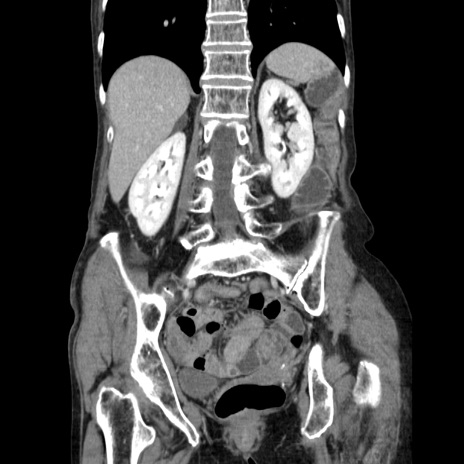

症例25(冠状断像)

【症例】80歳代女性

【主訴】胸のつかえ感

【現病歴】約9時間前に食後から胸のつかえた感じあり、嘔吐あり、来院。

【既往歴】胃癌(全摘)、胆摘、虫垂炎

【身体所見】心窩部に圧痛あり、反跳痛なし。

【データ】WBC 5700、CRP 0.05